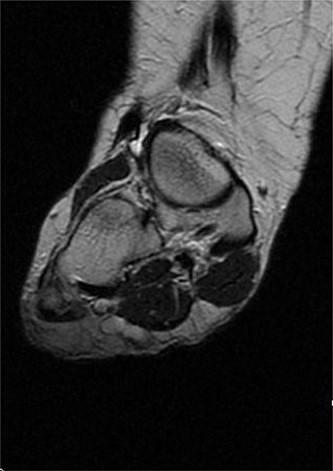

USS described this swelling in the plantar aspect of the midfoot as a well-defined, hypoechoic tender lesion within the plantar subcutaneous tissue measuring ~17 × 7 × 11 mm. More importantly, the lesion extended deep to the plantar fascia not arising from it, hence ruling out plantar fibromatosis (Fig. 1). In order to rule out any aggressive pathology, a magnetic resonance imaging (MRI) with contrast was arranged, which revealed a 2 cm by 5 mm tubular oblique lesion in the plantar subcutaneous fat. MR imaging was also able to rule out sinus tarsi syndrome and any internal derangements (Figs 2 and 3). She was referred to Orthotics for a medial support arch to help with pain. Since the exact characteristics of this lesion were still unknown, the case was referred to the Yorkshire Sarcoma Multi-disciplinary team (MDT). The outcome of this meeting concluded that there were no radiological features of a sarcoma. She still experienced an excruciating, sharp stabbing pain in her right foot. Pain score was 10/10. She opted for the surgical excision biopsy of the lesion. The post-operative period was uneventful with good healing of the wound. She was followed up 2 months, and with the histology findings, results revealed a rare soft tissue neural neoplasm in keeping of a neurofibrolipoma. The patient was happy with the overall outcome and was discharged. She was reviewed again after 2 years for a further foot and ankle problem in the other foot, and at the time of review, she was completely pain-free in the right foot with an excellent outcome.